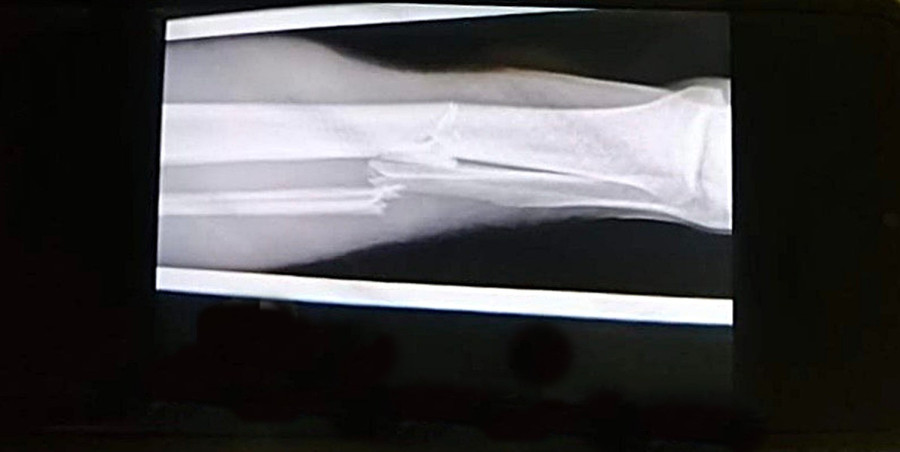

A Balaton Bútor FCV csapatkapitány-helyettese, Boromisza Dániel szárkapocscsont- és sípcsonttörést szenvedett a házigazda Debrecen elleni hétfő esti alapszakasz mérkőzésen.

A Magyar Kupa-címvédő klub keddi közleményéből kiderült, hogy Boromisza Dánielt még hétfőn este megműtötték; a beavatkozás pedig sikerrel zárult.

A kiérkező mentősök diagnózisa helyesnek bizonyult - Fotó: futsalveszprem.huA kiérkező mentősök diagnózisa helyesnek bizonyult - Fotó: futsalveszprem.hu

A játékos sípcsontjába egy szöget helyeztek a térdétől egészen a bokájáig. Boromisza Dániel jelenleg a debreceni kórházban pihen. A veszprémi csapat kollégái a hét második felében fogják hazaszállítani Veszprémbe. Ahogy a szurkolók, úgy a társai is nagyon aggódtak a csapatkapitány-helyettesért, aki elárulta, ma már sikerült mosolyognia is.

A közleményből továbbá azt is leírták, hogy Boromisza Dániel a 2021/2022-es idény további részében már biztosan nem lép pályára; felépülési ideje várhatóan 6-8 hónap lesz.